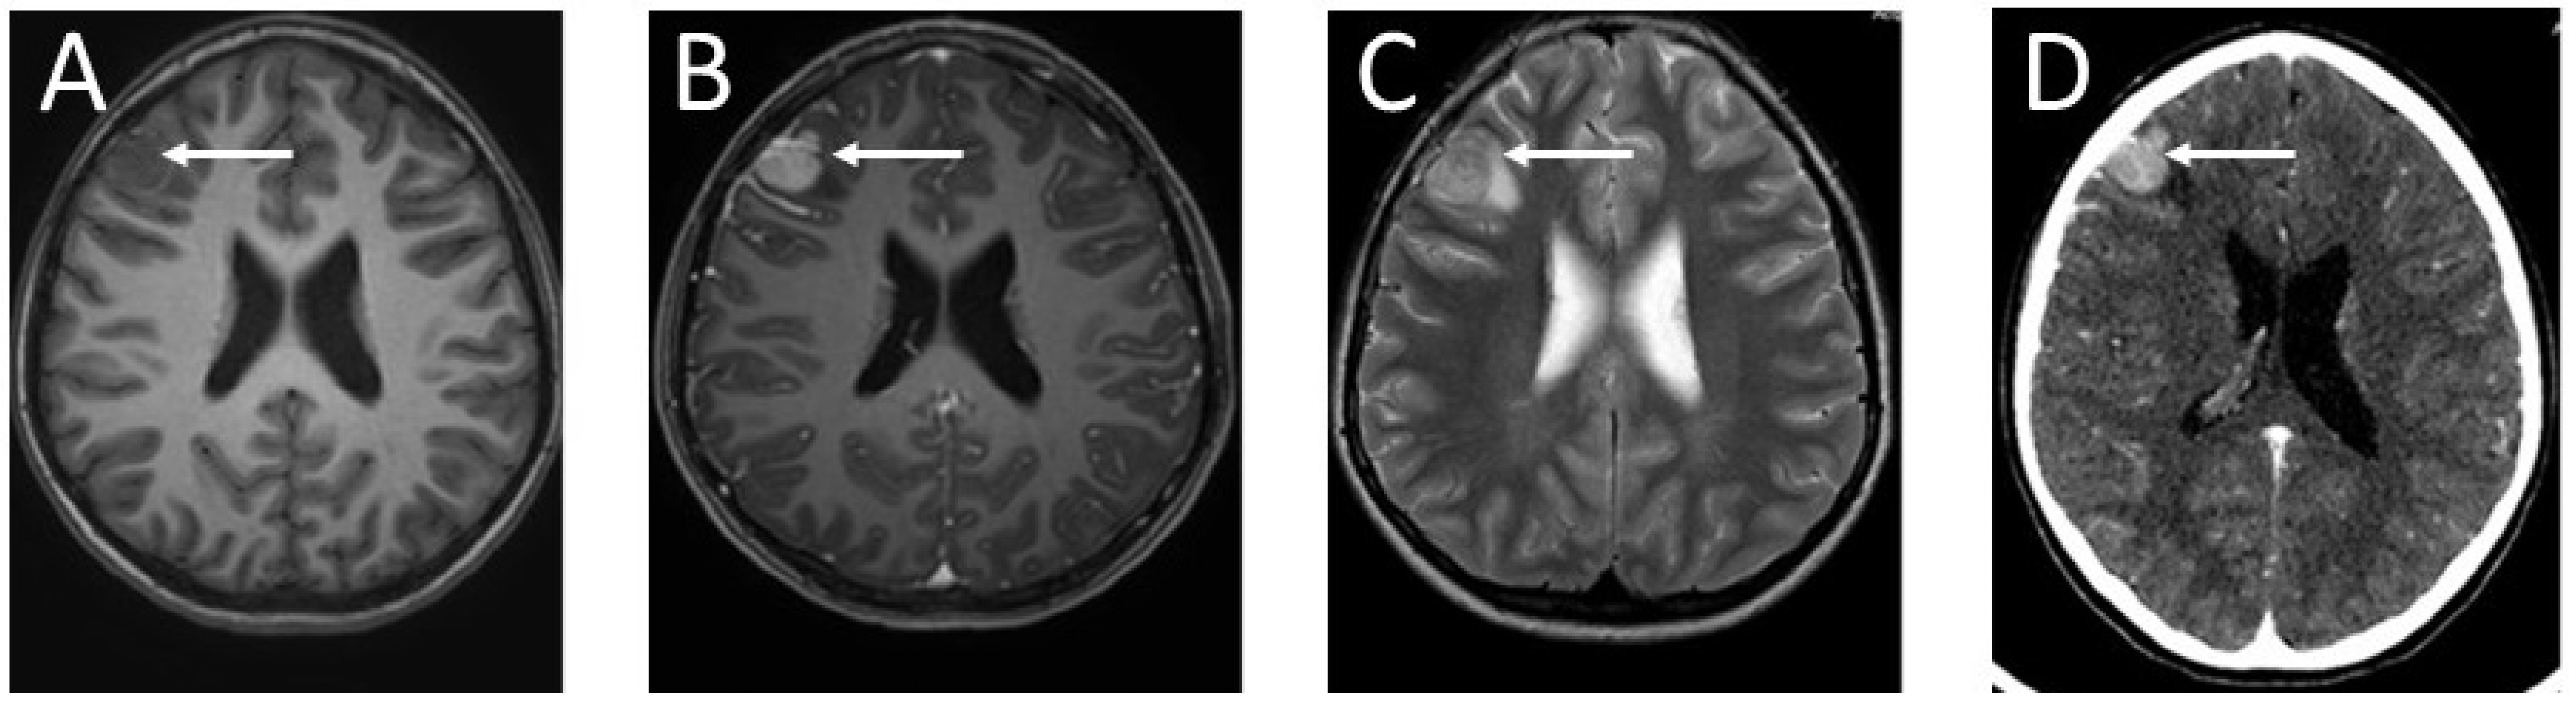

2. Case Presentation